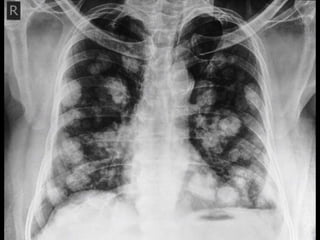

Cannon Ball Metastasis